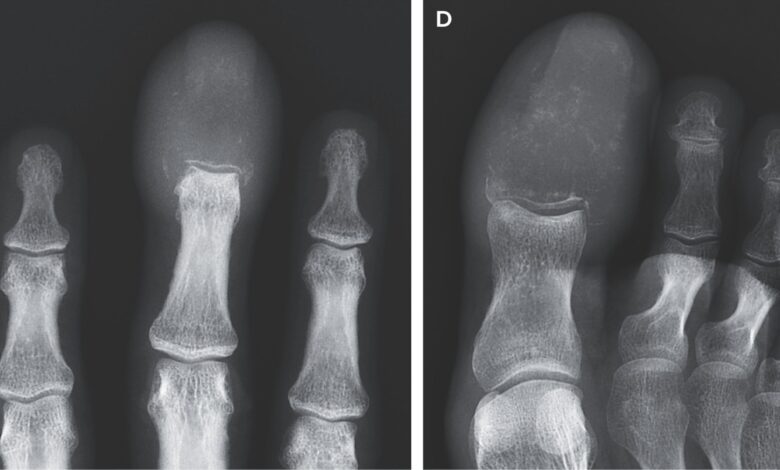

Skenování postižených rukou a nohou člověka odhalilo „destruktivní lytické léze, které zcela nahradily„ kosti v špičkách prostředního prstu a velké prsty. Lytické léze jsou oblasti, kde byla zničena kost, a v kostru ponechávají otvory nebo prázdné prostory. Takové léze jsou obvykle poháněny procesem onemocnění rakovina.

Rakovina, která se rozšířila do prstů nebo kostí prstů, může napodobit dnu nebo osteomyelitidu při fyzickém vyšetření, ale skenování zvané rentgenové snímky může pomoci diagnostikovat stav, poznamenali lékaři pacienta. Dna je forma zánětlivé artritidy a osteomyelitida Způsobuje zánět v kostech, často v důsledku infekce, takže obě podmínky mohou způsobit viditelné zarudnutí a otoky.

Na základě jeho rentgenových snímků byl muž diagnostikován s akrometastázou, relativně vzácnou formou šíření rakoviny, která se vyskytuje pod loktem nebo kolenem. Acrometastázy představují pouze asi 0,1% případů, kdy se rakovina rozšířila do kostí, podle a 2021 Recenze.